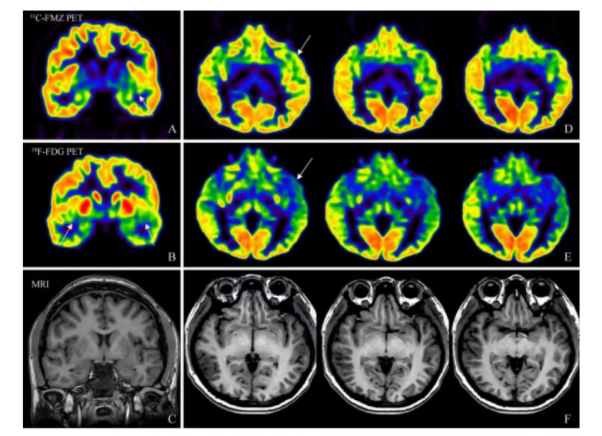

传统的癫痫病灶定位依赖于磁共振、脑电图及¹⁸F-FDG PET(氟代脱氧葡萄糖正电子发射断层扫描)等技术组合。其中,¹⁸F-FDG PET通过显示脑部葡萄糖代谢异常来指示病灶,但往往定位范围较广,特异性有限。为提升精度,北部战区总医院的研究团队引入了¹¹C-FMZ PET(氟马西尼正电子发射断层扫描)显像技术。¹¹C-FMZ能特异性结合大脑内γ-氨基丁酸苯二氮䓬受体,而该受体数量在致痫灶区域通常减少,从而实现对病灶的分子水平精准示踪。

研究团队对17名药物难治性癫痫患者进行了回顾性分析。这些患者在术前均接受了¹¹C-FMZ和¹⁸F-FDG PET/MR一体化扫描。结果显示,两种技术优势互补:¹⁸F-FDG PET在判断致痫灶位于大脑哪一侧时表现出高准确性(94.1%),并能有效提示多发病灶的存在;而¹¹C-FMZ PET在精确定位病灶具体位置方面表现更优,准确率达88.2%,尤其对于海马硬化等常见单一病灶,其识别具有高度特异性,避免了传统方法定位范围过大的问题。

该双核素显像策略的核心价值在于,将反映脑代谢的¹⁸F-FDG与靶向特定受体的¹¹C-FMZ相结合,实现了对致痫灶从“功能异常区域”到“特异性病理靶点”的双重验证。两种显像剂均为临床成熟用药,安全性已得到广泛验证。¹⁸F-FDG为葡萄糖类似物,参与正常代谢;¹¹C的半衰期较短(约20分钟),检查后体内辐射水平迅速降低。